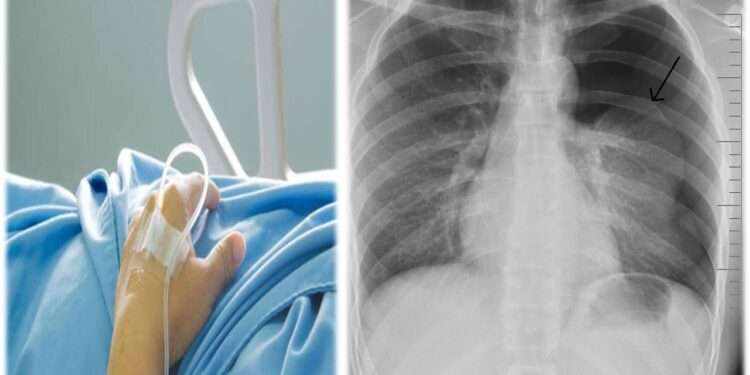

صدى الشعب – أكد مرافق نجل رئيس الوزراء الأسبق، أسعد سعد جمعة أن (جمعة الابن)، دخل في غيبوبة من جديد، دون أن يوضح تفاصيل.

و لكن لاحقاً لعدد من المناشير، بدأها بـ(تم نقل اسعد سعد جمعه للمستشفى الآن إثر نزيف داخلي حاد، الرجاء الدعاء له بالشفاء العاجل، ليكمل في منشور آخر بعد دقائق: “يؤسفني اخباركم بأن قلب السيد أسعد توقف والأطباء يسعون لانعاشه كهربائياً.”

ثم أخيراً في شرح حالته الصحية التي يُرثى لها قال: “الحمد والشكر لله، بدأ قلب اسعد سعد جمعه بالنبض ،ولكن تم كسر ضلعين لأنهم اضطروا لاستعمال ٤٥٠ ك جول.

يذكر أن نجل رئيس الوزراء الأسبق، خرج في الكثير من المواقع الإلكترونية و المؤسسات الإعلامية، مشيراً أنها تعرض للظلم من أشخاص بعينهم، حرموه من ورثة والده، ألأمر الذي جعله حبيس المنزل للمطالبات المالية و حباس المستشفيات و أسرة (الـicu , ccu)..